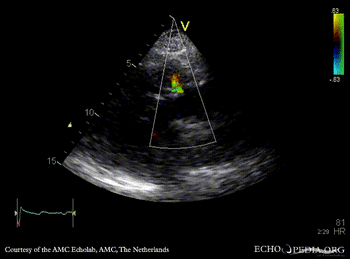

Fistula from ascending aorta to the right ventricle

PLAX: color doppler, fistula from ascending aorta to the right ventricle Continuous-wave signal of flow through fistula